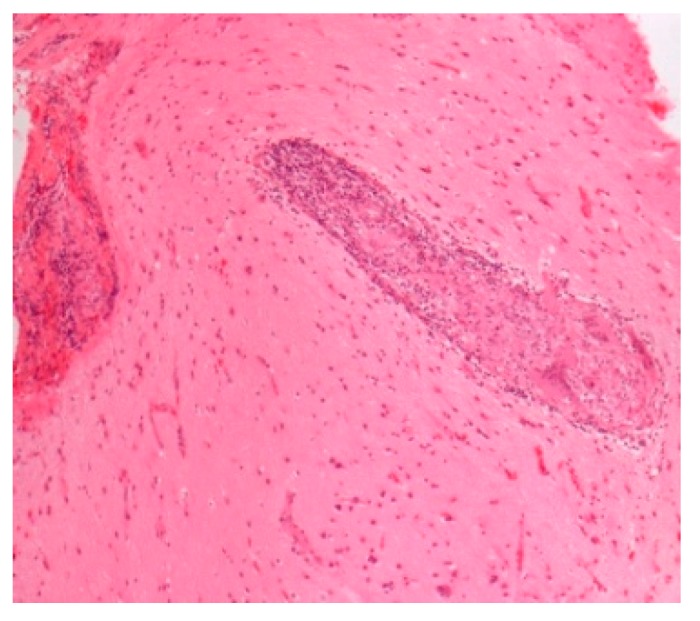

Pathology images of the spectrum of pediatric sarcoidosis involving different organs (Figure 1, Figure 2, Figure 3, Figure 4, Figure 5, Figure 6 and Figure 7).

| -Prevalence-Systems involved-Prognosis | -0.22–0.29/106-Lymph nodes/Lung-Chronic disease 12% | BAL: CD4/CD8Biopsies | GranulomasFigure 1 | [ref. 2,ref. 8,ref. 11,ref. 13,ref. 15] |

| High-risk sarcoid-Treatment-resistant Pulmonary sarcoid-Cardiac sarcoid/CS-Neurosarcoid/ NS | -Most common, progression to chronicity -CS Case reports-NS 53 cases | Chest XR, CT,EBUS/TBNA Cardiac echoCT /MRI | Figure 2 Figure 3Figure 4 | [ref. 2,ref. 9,ref. 13];[ref. 2,ref. 6,ref. 8,ref. 14,ref. 34,ref. 46] |